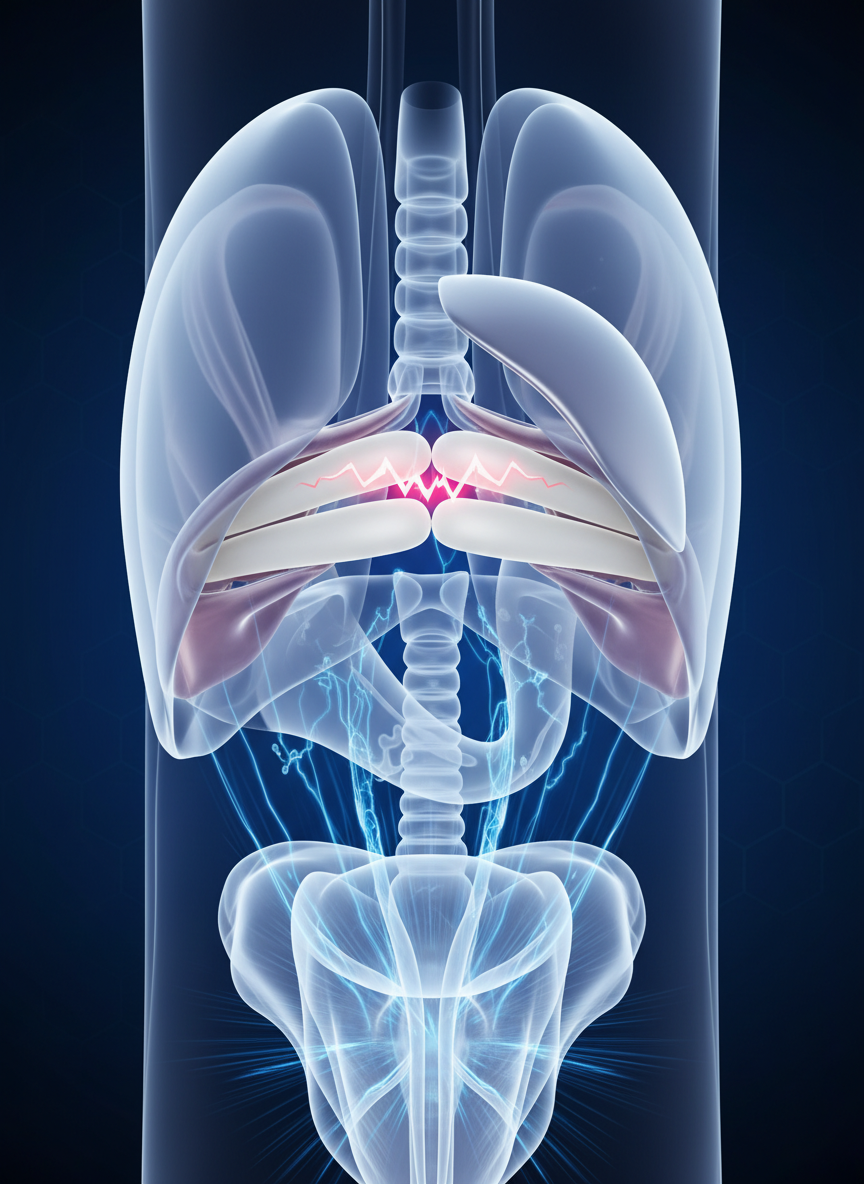

딸꾹질은 의외로 우리 몸의 아주 특별한 근육, 바로 횡격막의 비자발적인 경련 때문에 발생해요. 이 횡격막이 갑자기 수축하면서 폐로 공기가 빠르게 들어오고, 이때 성대가 닫히면서 '히끅' 하는 소리가 나는 거죠. 생각해 보면 정말 신기한 현상이죠?

주로 미주신경이나 횡격막 신경이 자극을 받을 때 이런 현상이 나타나는데, 사실 대부분은 크게 걱정할 필요 없는 일시적인 경우가 많아요. 제가 겪어본 바로는 너무 급하게 식사를 하거나, 갑자기 차가운 음료를 마시거나, 스트레스를 많이 받으면 여지없이 딸꾹질이 찾아오곤 하더라고요.